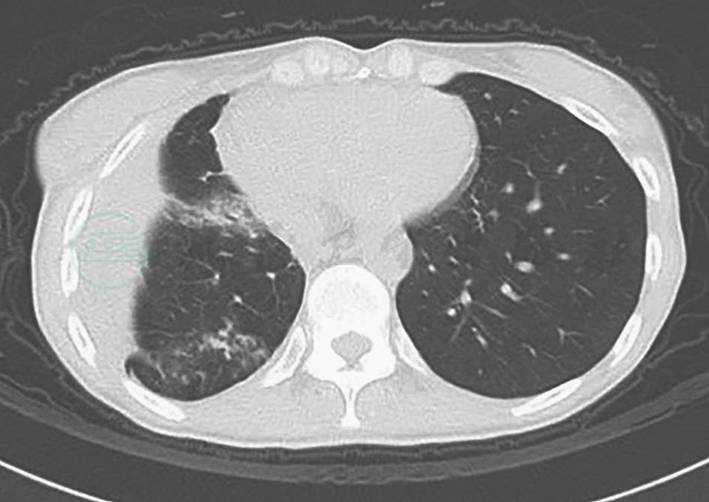

2010年1月患者无明显诱因出现咯血,为痰中带血,无低热、盗汗、消瘦等不适,肺CT片提示“右肺下叶两个不规则空洞,壁厚薄欠均匀,边缘较毛糙,内壁尚光滑,空腔不规则并见分房,局部胸膜轻度牵拉增厚”(图1),血及肺泡灌洗液的曲霉半乳甘露聚糖(GM)检测均阳性,痰真菌培养、细菌培养及痰找抗酸杆菌均阴性,肺泡灌洗液细胞分类正常,结核菌素纯蛋白衍生物(PPD)试验阴性,肿瘤标志物不高,考虑患者为“肺类风湿结节坏死、肺烟曲霉感染、肿瘤不除外”,建议行肺穿刺活检明确病变性质,但患者拒绝。予患者口服伊曲康唑200mg/d,抗真菌感染治疗2个月后,复查胸部CT空洞无好转,遂行右下肺叶切除术,病理提示“肺内多发结节,部分结节中心坏死,炎性渗出,周围纤维结缔组织增生包裹,淋巴细胞浸润,可见个别巨细胞。另有部分结节纤维化,炎症细胞浸润。病变内及周围血管疑有血管炎病变。支气管断端未见明显异常,支气管周边淋巴结反应性增生”。特殊染色结果:弹力纤维染色(+),抗酸染色(−)。考虑为“类风湿结节可能”。此后咯血好转。

图1 2010年1月胸部CT

A、B中箭头示右肺下叶不规则空洞